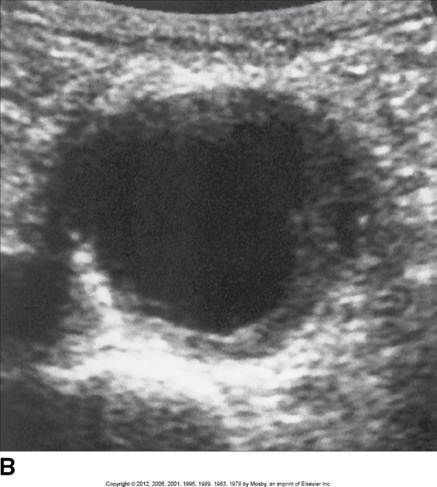

Abdominal Aortic Aneurysm (AAA):

Transverse aortic aneurysm with thrombus